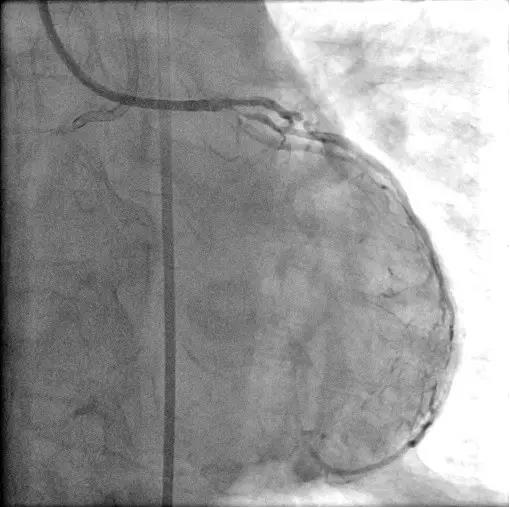

前降支90%狭窄